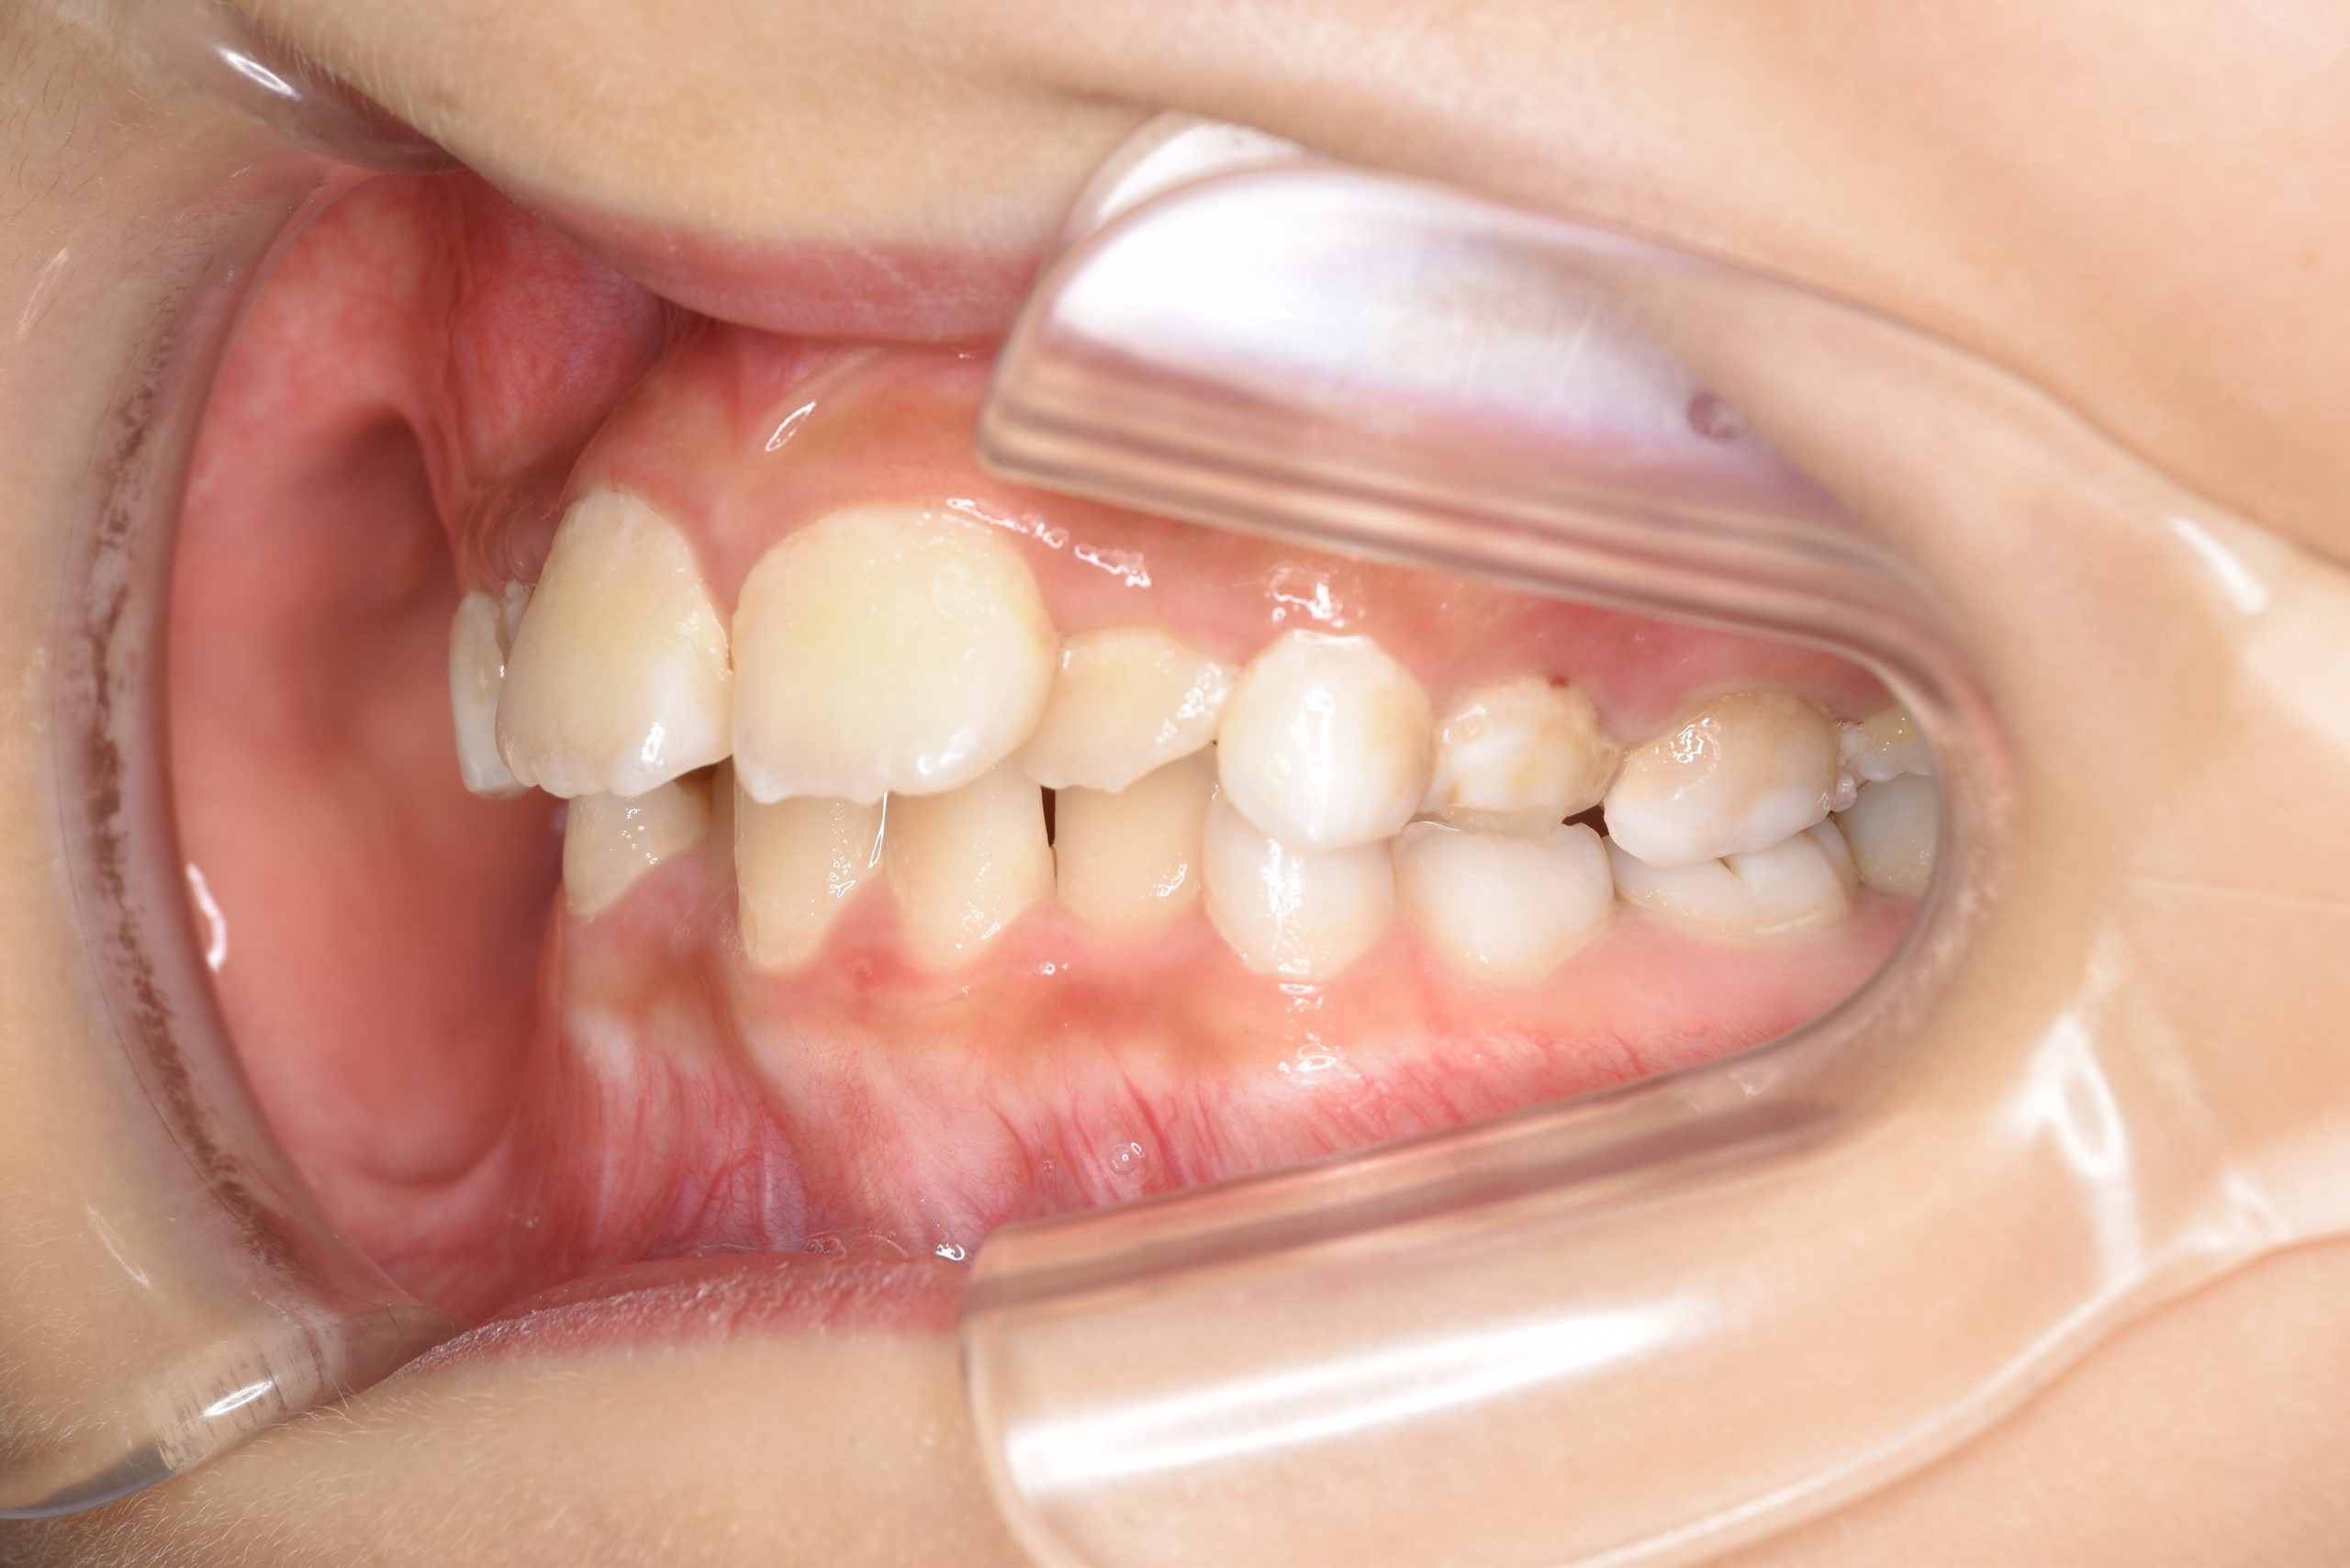

全顎ワイヤー矯正 症例_185

主訴 歯並び|横から生えている大人の歯

施術内容 小児矯正1期治療

治癒期間 4年間

費用 522,960円(税込)